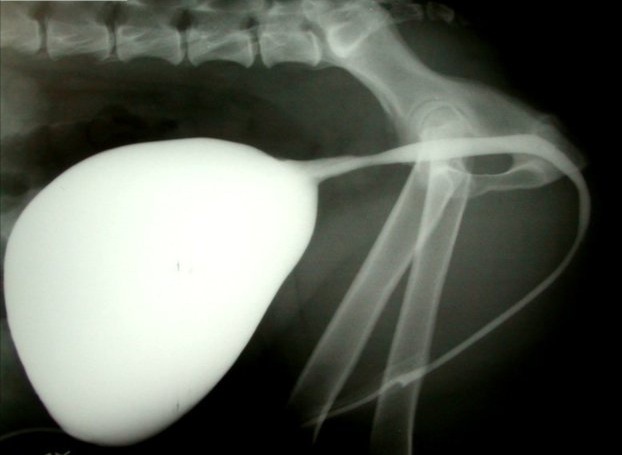

no evidence of structural obstruction

what do you need to know to solve this dog’s problem?